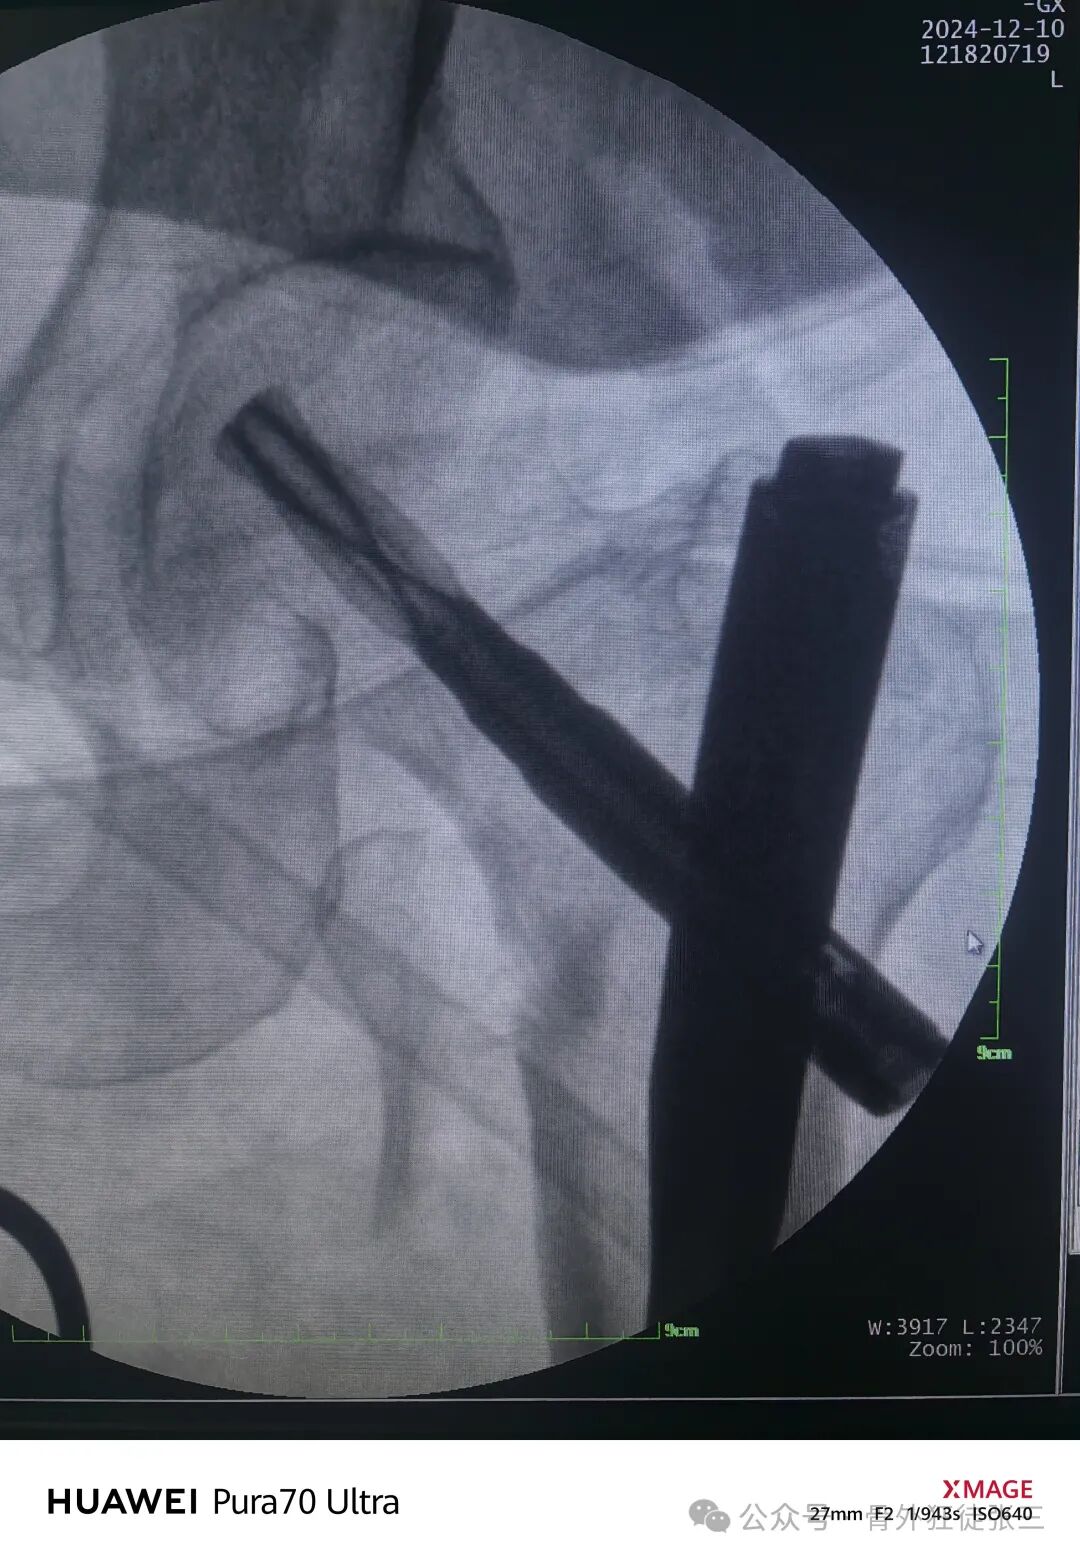

使用微创牵开器

3分钟安装

骨钩从切口入股骨颈复位

再次透视

正位复位满意

导针正位中下1/3

骨钩过牵了

有点阴性支撑

侧位导针居中

远端静态锁定

术中出血约50ml

手术从切皮到缝合

40分钟结束

透视18次